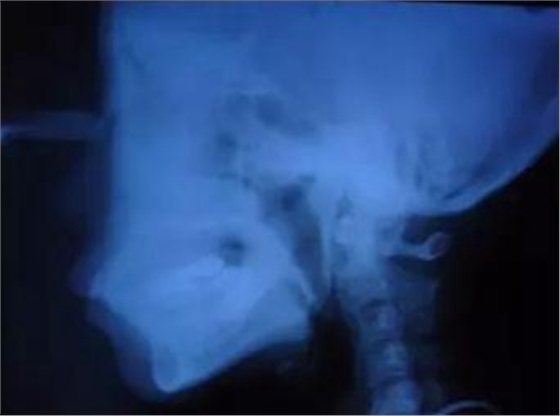

▲ 圖2 典型病例矯治前,患者牙(牙合)像、曲面斷層、頭顱側(cè)位片及側(cè)面像